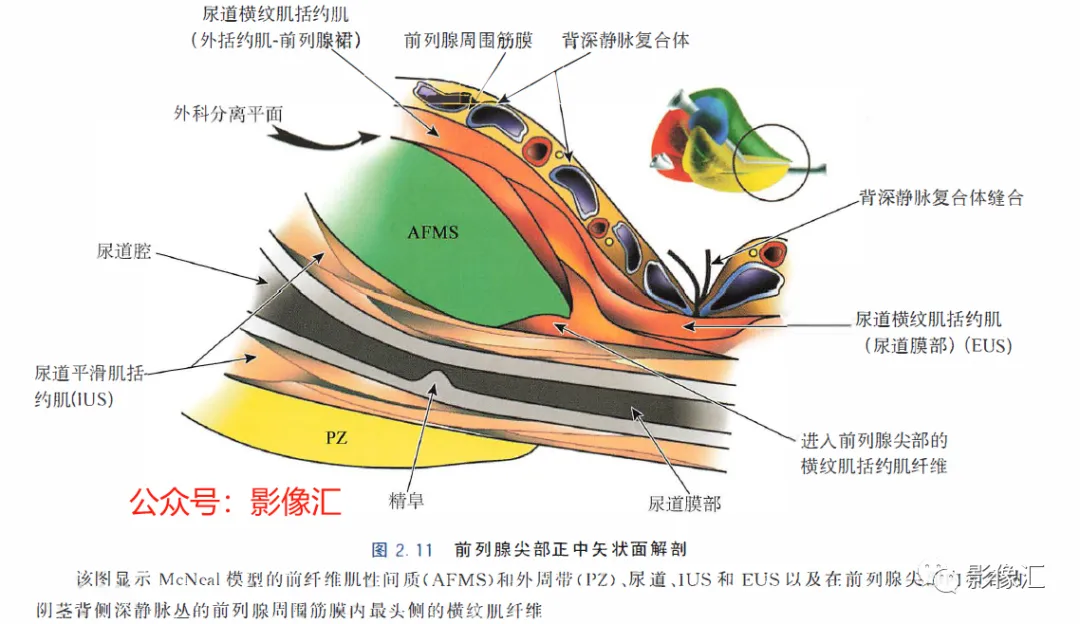

前列腺尖部是用于表示前列腺腺体尾侧(最下方)的术语,与尿道膜部密切接触。前列腺尖部可显示出不同的形态:圆环形或腹侧,背侧或两侧突出(图2. 9和图2.10) ,了解前列腺尖部形态的重要性主要在于两点:(1)前列腺尖部或多或少与EUS(尿道膜部的横纹肌纤维)头侧区域重叠(或覆盖),这些纤维部分融入前列腺尖部(图2.11)。在接受根治性前列腺切除术的患者中,有必要采用能够外翻(exteriorising)和解剖这部分横纹肌纤维的手术技术, 以保持控尿功能(图2.12)。(2)在根治性前列腺切除术中必须避免阳性边缘 。值得注意的是,在尖部水平,腺体组织仅为外周带组织,尖部仅前缘一小部分为AFMS。此外,前列腺尖部构成所谓的梯形区域的顶部,这是众所周知的解剖薄弱区域,在该区域前列腺癌可更易侵犯至前列腺间隙(图2.8)。在其前外侧,前列腺尖部由外括约肌群覆盖,与AFMS及从膀胱颈延伸来的由平滑肌构成的逼尿肌群相融合(图2. 13)。前列腺尖部尾侧与尿道膜部起始部相延续。男性的尿道膜部被认为是位于前列腺尖部和尿道球部之间的尿道部分,长度约为1cm。其内有尿道内括约肌(IUS)和尿道外括约肌(EUS)。IUS从膀胱颈(此处最厚)延伸到尿道球部,沿尾侧方向厚度逐渐减小。IUS环尿道膜部,由双层平滑肌纤维组成,包括内层纵行肌和外部的环形肌(图2. 13和图2. 14)。IUS的神经支配来自自主神经、交感神经和副交感神经系统。下腹下神经丛负责前列腺、前列腺尖部和尿道膜部的所有自主神经支配。其终末支沿内侧走行达耻骨上肌,外侧走行达尿道膜部的EUS,在腹侧构成所谓的阴茎海绵体神经(负责勃起机制)和尿道海绵体神经(负责尿道膜部黏膜的自主神经传入,直接与控尿机制有关(图2 . 13 和图2. 14)。EUS构成横纹肌平面(横纹肌纤维),在尿道膜部水平围绕IUS,在前列腺尖部的前外侧上扩展,并在该水平上构成所谓的EUS围裙(图2. 13)。其肌纤维主要是I 型(即没有肌梭),尽管强度低,但专门负责长时间收缩。EUS的功能在于排尿间期保持尿道腔塌陷,从而防止无意识的尿液渗漏。EUS最厚处位于尿道膜部水平,厚度向头侧逐渐减小,最终构成前列腺围裙。该围裙以Ω(希腊字母“欧米伽”)形围绕尿道膜部,而后正中不包绕, 形成“后正中脊”(图2. 13 和图2. 14)。此外,EUS的部分横纹肌纤维融入到前列腺尖部的下部,位于精阜下方,融入纤维的多少依赖于前列腺尖部形态(图2. 11) 。EUS的神经支配和动脉供血分别来自外阴神经和外阴内动脉。该神经为躯体神经,因此EUS可随意控制。外阴内神经和动脉均向头侧走行,至会阴深横肌处,发出分支支配EUS最尾侧部分,随后形成阴茎背侧神经脊背侧动脉。前列腺尖部与支配EUS的外阴内动脉的分支之间距离为3~13mm (图2. 13)。IUS和EUS构成所谓的控尿被动及内在因素。它们的功能基本上是“塌陷”尿道至“后正中脊”,这样可防止排尿间期无意识的尿液“泄露”(图2.11和2.13)。阴茎海绵体神经在前列腺周围筋膜的后外侧及前外侧走行。手术操作时保留这些外侧神经对于确保前列腺根治术后勃起功能的恢复是至关重要的。会阴体是一纤维肌性结构,难以在解剖上进行评估,其功能是支持所有构成会阴部及支撑盆腔脏器的肌肉及腱膜结构。对于控尿,会阴体形成一固定的底盘,通过将EUS的横纹肌平面压至底盘处,从而可使EUS正确发挥功能,这样在排尿间期可以正确地使尿道塌陷。会阴体由以下结构组成(图2.13)和图2.14)。

根治性前列腺手术有两个主要目标:完全切除肿瘤和令人满意的术后功能,即控尿及阴茎勃起功能的恢复。为了在根治性前列腺切除术后实现早期控尿恢复,需要完全保留尿道括约肌系统,同时保留耻骨直肠肌和耻骨会阴肌(后者更为重要)。EUS的保存始于在腺体顶端前外侧上彻底分离EUS裙,向尾部方向操作。根据尿道周围筋膜,可正确识别和分离尿道膜部的EUS,这是阴茎海绵体和尿道海绵体神经未梢的位置(图2.12 至图2.14) 。AFMS和前列腺尖部的MRI评估可以显示这些区域中存在肿瘤,或者为主要病灶区域,或者更常见的是,MRI可以显示最初其他解剖区域的肿瘤对AFMS和(或)前列腺尖部的局部累及。这些情况下,在这个水平由于造成阳性切缘的风险很高,因此括约肌保留手术是禁忌的。